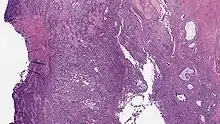

Undifferentiated uterine sarcoma

Undifferentiated uterine sarcoma, or undifferentiated (high-grade) endometrial stromal sarcoma, does not resemble normal endometrial stroma and behaves much more aggressively, frequently metastasizing. The differential includes leukemia, lymphoma, high-grade carcinoma, carcinosarcoma, and differentiated pure sarcomas.

Microscopy

- Monotonous ovoid cells to spindly cells with minimal cytoplasm.

- Prominent arterioles. Angiolymphatic invasion common.

- Up to 10-15 mitotic figures per 10 HPF in most active areas.

- Tongue-like infiltration between muscle bundles of myometrium.

- May exhibit myxoid, epithelioid and fibrous change.

- May have foam cells or hyalinization in the stroma.